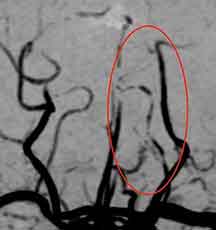

症例1. 可逆性脳血管攣縮症候群

30代の女性で、20歳頃から時々頭痛がありました。

筋トレ中、急に後頭部の激しい頭痛が出現しました。約20分でいったん頭痛は軽くなり、帰宅しました。しかし、その後も運動する度に頭痛が悪化し、数日が経ちました。何か脳の重大な病気ではないかと心配になり、当院を受診しました。

頭部MRA検査を見たところ、

後大脳動脈が所々で途切れたようになっており、可逆性脳血管攣縮症候群と診断しました。

この疾患では、交感神経系の過剰反応が関係します。つまり、緊張や興奮が一気に頂点に達する動作で誘発されます。

症状は数週間から1ヶ月で自然に改善するとされています。しかし、それまでの間強い頭痛に悩まされる事になり、生活に大きな支障をきたします。

そこで、横浜脳神経内科では可逆性脳血管攣縮症候群の診断と治療に力を入れています。まず第一にくも膜下出血など重大な脳の病気を除外し、早期に適切な治療を開始することが大事です。この方は、血管拡張薬と交感神経遮断薬、鎮痛剤で治療する事となりました。